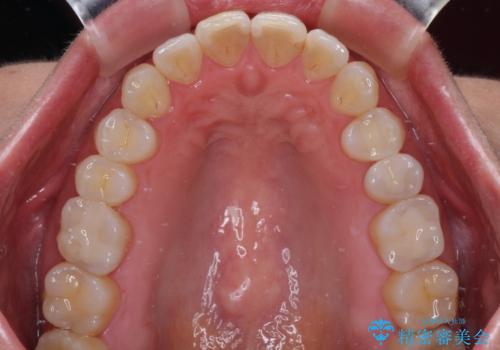

自然な色調で大変満足されました。